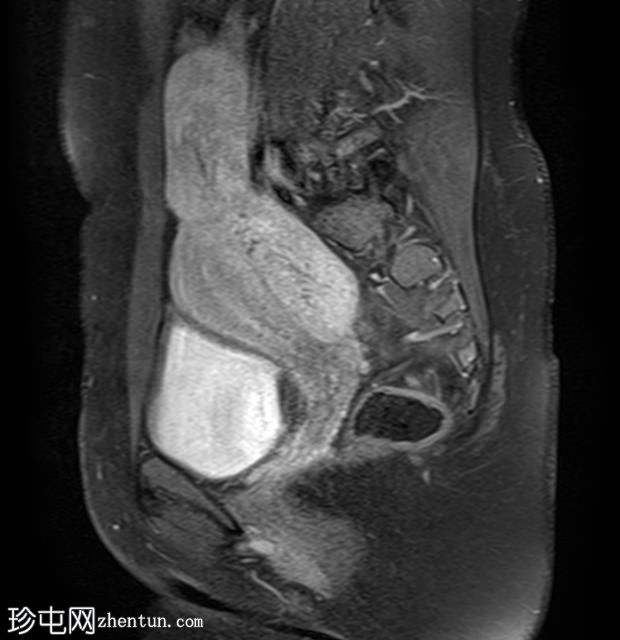

轴位T1加权像

增强脂肪抑制像

盆腔内可见多个边界清晰的肿块:

其中一个位于子宫上方,T2加权像呈中等信号,中心区域呈高信号,增强T1脂肪抑制像未见强化。右侧卵巢增大,增厚的血管蒂扭曲,未见强化,轴位和矢状位T2加权像均显示清晰。

另一个位于子宫后窝,T2加权像呈中等信号,增强扫描显示明显强化。

2个月前进行的MRI检查显示双侧卵巢肿块均有强化,右侧卵巢肿块未见扭转。